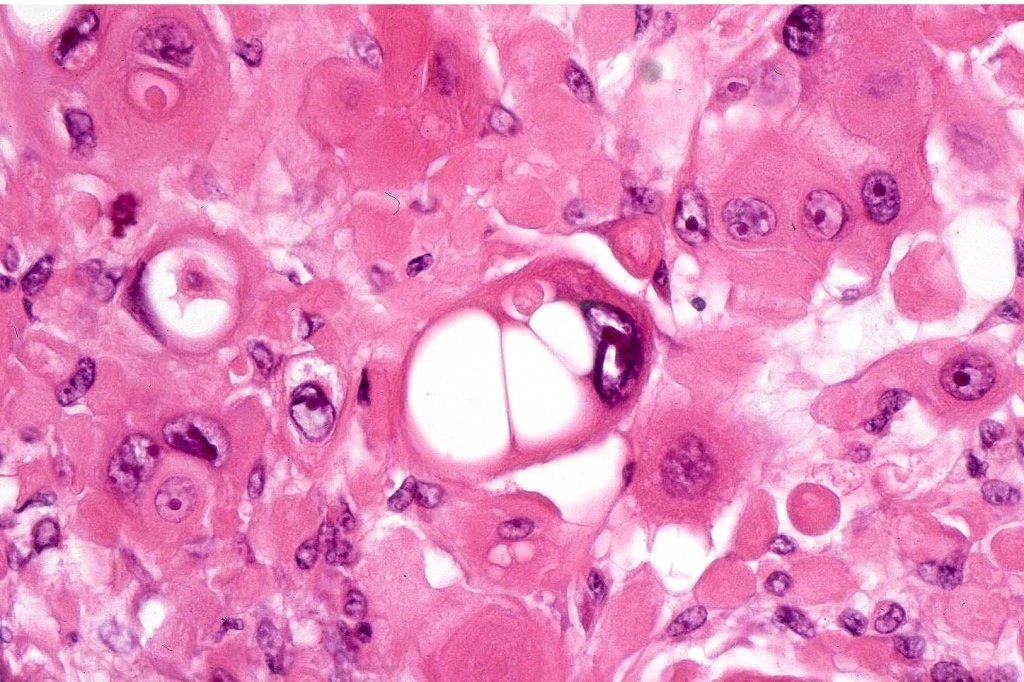

•Acantholysis gives rise to a pseudoglandular appearance

•Often well differentiated

•Variable pleomorphism & mitotic activity